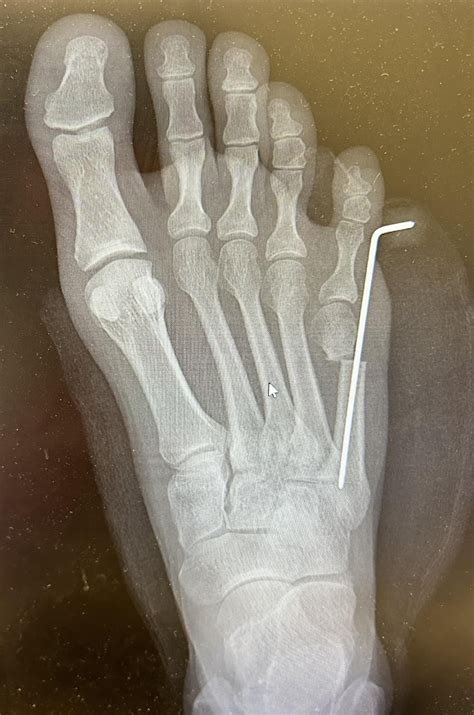

If you have diligently followed conservative treatment plans for several months without experiencing relief, your podiatrist may suggest surgical options. Surgery for treating tailor’s bunion involves removing the bony prominence or realigning the metatarsal bone to fix the structural issue permanently.